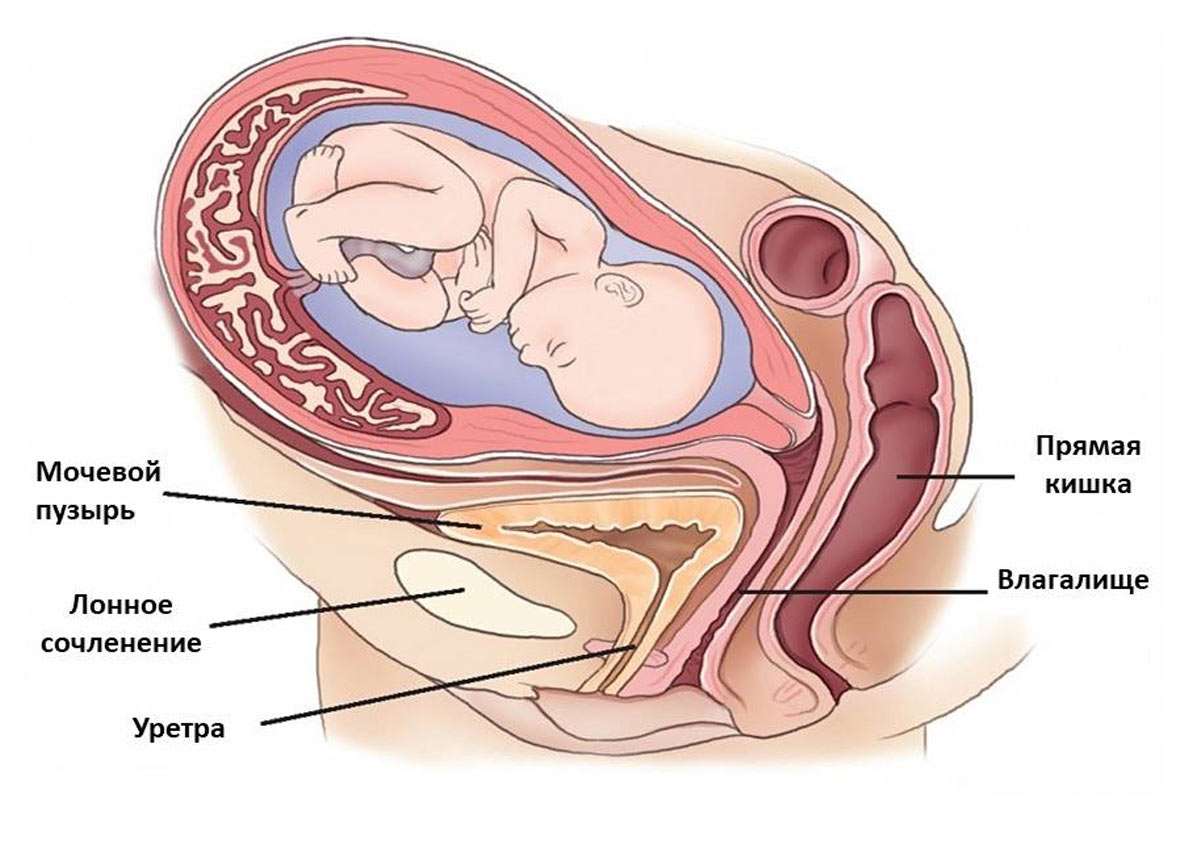

Заблуждения и факты о внутрибрюшной беременности